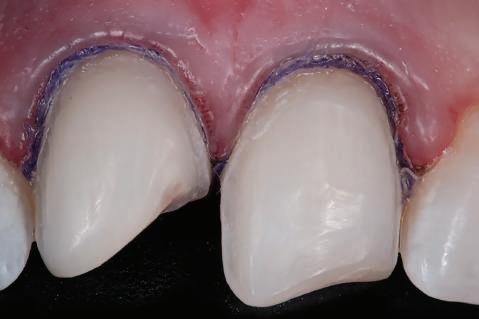

Datorită stabilității primare la inserare de aproximativ 35 Ncm pentru ambele implanturi, am optat pentru înșurubarea bonturilor intermediare conice Balance Base Narrow Straight GH 3.0 și vindecare transgingivală (fig. 2, 3). Inserarea acestor stâlpi s-a realizat la un cuplu de forțe de 25Ncm, cu ajutorul unei chei dinamometrice, aplicându-se ulterior cape de protecție (fig. 4). Vindecarea transgingivală postoperatorie a decurs fără complicații.

Figurile 1. Status clinic şi radiologic iniţial; 2. Bontul Balance Base Narrow Straight GH 3.0; 3. Bonturile Balance Base Narrow aplicate imediat post-inserare la 25 Ncm; 4. Aplicarea capelor de protecţie şi sutura; 5. Stâlpii de amprentă înşurubaţi la nivelul bonturilor Balance Base Narrow;